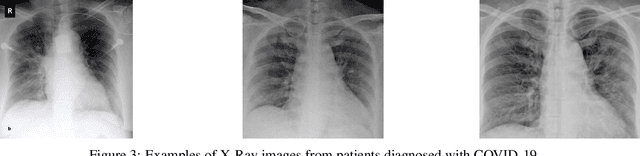

Abstract:The coronavirus outbreak became a major concern for society worldwide. Technological innovation and ingenuity are essential to fight COVID-19 pandemic and bring us one step closer to overcome it. Researchers over the world are working actively to find available alternatives in different fields, such as the Healthcare System, pharmaceutic, health prevention, among others. With the rise of artificial intelligence (AI) in the last 10 years, IA-based applications have become the prevalent solution in different areas because of its higher capability, being now adopted to help combat against COVID-19. This work provides a fast detection system of COVID-19 characteristics in X-Ray images based on deep learning (DL) techniques. This system is available as a free web deployed service for fast patient classification, alleviating the high demand for standards method for COVID-19 diagnosis. It is constituted of two deep learning models, one to differentiate between X-Ray and non-X-Ray images based on Mobile-Net architecture, and another one to identify chest X-Ray images with characteristics of COVID-19 based on the DenseNet architecture. For real-time inference, it is provided a pair of dedicated GPUs, which reduce the computational time. The whole system can filter out non-chest X-Ray images, and detect whether the X-Ray presents characteristics of COVID-19, highlighting the most sensitive regions.